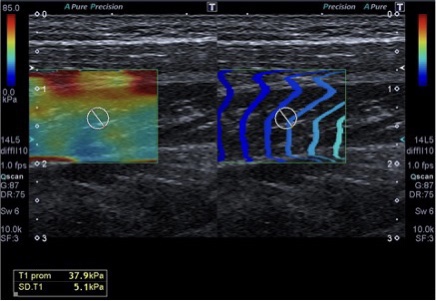

357. Kilopascales (kPc) en Elastrografía. Lo que el TSID debe saber.

Cuando hablamos de medicina moderna, las tecnologías de imagen han revolucionado la forma en que diagnosticamos y tratamos una variedad de enfermedades. Entre estas tecnologías se encuentra la elastografía, un método no invasivo para evaluar la rigidez de los tejidos internos del cuerpo. Pero, ¿alguna vez te has preguntado cómo se mide esta rigidez? Aquí es donde entran en juego los kilopascales (kPa). En este post, exploraremos qué son los kilopascales, su importancia en la elastografía y cómo se utilizan en la práctica médica.

La Importancia de los Kilopascales en Elastografía

La elastografía es una técnica que mide la rigidez o elasticidad de los tejidos blandos, como el hígado, los músculos y otros órganos. Esta técnica es especialmente valiosa para detectar cambios en la rigidez del tejido que podrían indicar condiciones médicas como fibrosis, cirrosis o tumores. En el ámbito de la elastografía, las medidas de rigidez se expresan típicamente en kilopascales.

• Evaluación Musculoesquelética: Utilizado en ortopedia para evaluar la rigidez de músculos y tendones.

Valores Normales de Rigidez

En el Tejido Hepático

• Normal: Entre 4,0 y 5,8 kPa.

• Fibrosis leve: Entre 6 y 7 kPa.

• Fibrosis moderada: Entre 8 y 9 kPa.

• Cirrosis: Más de 12-14 kPa.

En Tejidos Musculares Principales

La rigidez de los músculos puede variar, pero generalmente son más duros (mayor rigidez medida en kPa) cuando están contraídos y más blandos cuando están relajados.